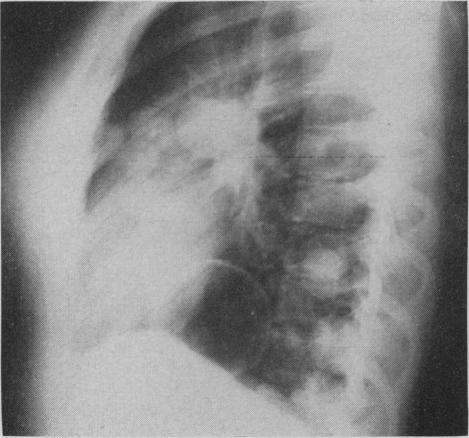

Pulmonary histoplasmosis.

Can Med Assoc J. 1959 Sep 15;81(6):486-8.